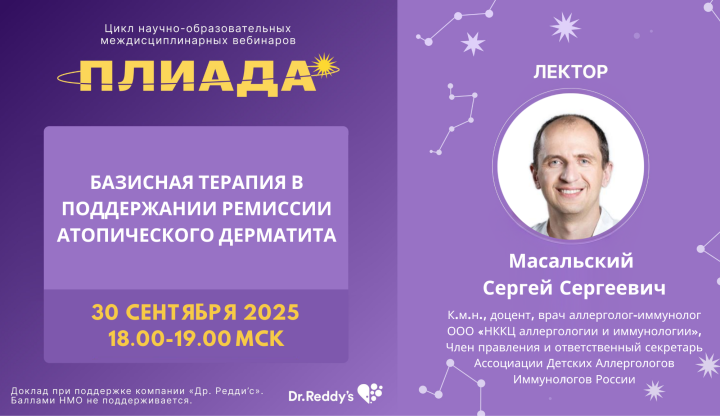

Базисная терапия в поддержании ремиссии атопическо...

Уважаемые коллеги! Приглашаем вас на вебинар «Базисная терапия в поддержании ремиссии атопического дерматита». В рамках цикла научно...

60 мин